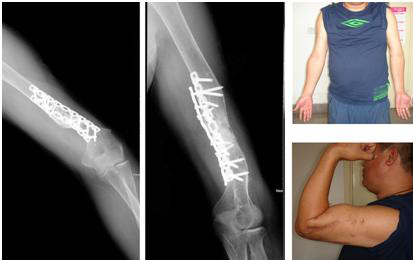

图2:术后6个月,人工骨完全吸收,骨折愈合,患者左上臂活动恢复正常。

FIGURE 2: Six months later, bone union occurred and left upper arm restored to

normal movement.